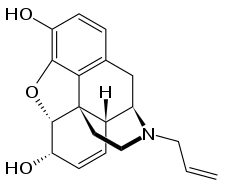

Several semi-synthetic opioids were developed in Germany in the 1910s. The first, oxymorphone, was synthesized from thebaine, an opioid alkaloid in opium poppies, in 1914.[228] Next, Martin Freund and Edmund Speyer developed oxycodone, also from thebaine, at the University of Frankfurt in 1916.[229] In 1920, hydrocodone was prepared by Carl Mannich and Helene Löwenheim, deriving it from codeine. In 1924, hydromorphone was synthesized by adding hydrogen to morphine. Etorphine was synthesized in 1960, from the oripavine in opium poppy straw. Buprenorphine was discovered in 1972.[228]